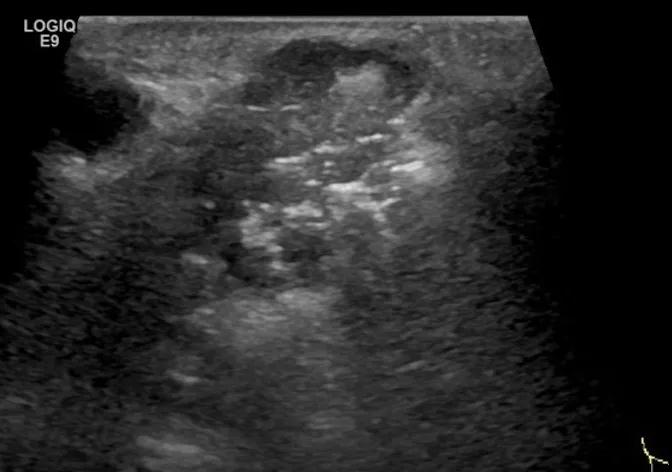

第二例是食管癌患者,术后半年余锁骨上固定淋巴结可触及肿大,疼痛非常明显,系统治疗后无缓解,患者希望通过局部处理缓解症状。造影显示强化信号明显,结节部分区域坏死,故主要针对强化区域从后向前的逐层的消融,皮下进行液体隔离减少烫伤。热消融后影像显示血流增强消失,弹性、硬度增高,一个月后复查显示充盈缺损,完全消融,疗效远超预期。

(病例2图例)